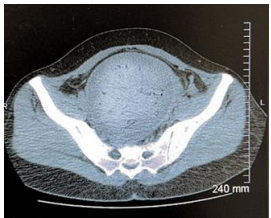

Further evaluation with MRI of the pelvis confirmed a grossly abnormal uterus containing a fluid-fluid and fluid-air level measuring 10 × 9 × 6 cm. Restricted diffusion was observed in the most posterior portion of the endometrial fluid collection, strongly indicating the presence of pus. An adjacent vaginal collection, measuring 10 × 9 × 8 cm, was also identified, but it did not show restricted diffusion, likely representing the prolapsed and necrotic portion of the fibroid (Figure 2 and 3 ). These findings were highly indicative of pyomyoma, necessitating immediate surgical intervention.

Figure 3 Pelvic MRI Axial view